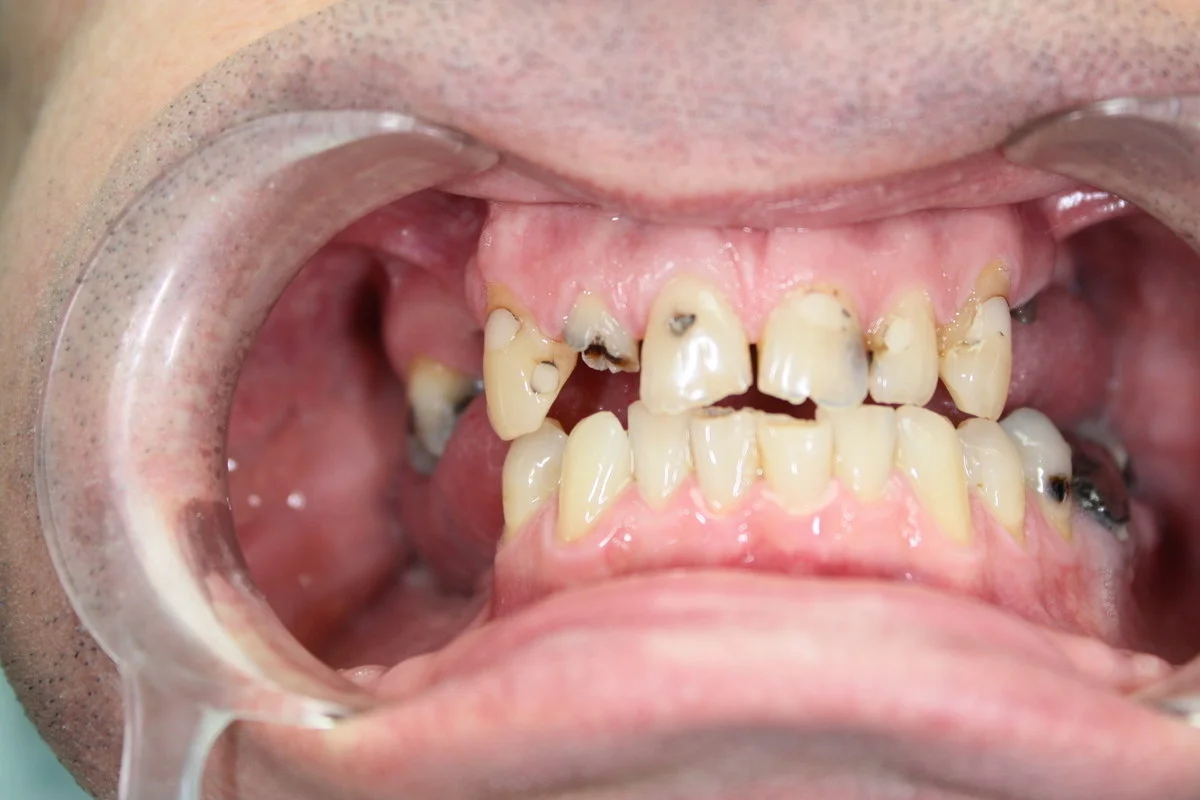

Dental bridges are used to replace one or more missing teeth, restoring chewing function and appearance. For a bridge to work, the teeth next to the gap must be strong and healthy enough to serve as supporting (abutment) teeth.

There are a lot of reasons why we lose our teeth. It can be aging, accidents or due to illness. Whatever the reason is, these factors will have a negative impact on your daily lives. You can not enjoy your favorite foods, lose your confident look, your cheerfulness, and your natural smile. if your teeth are restored. In case of missing teeth a dental bridge is available in a short period of time at reasonable costs.

A bridge can be applied if you have a tooth gap, but the adjacent teeth are healthy. In this case the teeth next to the gap are ground down and serve as pillars for the bridge. It is a 3 item bridge, made of 3 crowns and bridging one tooth gap. Traditional dental bridges can be applied to bigger tooth gaps where two or even three teeth are missing. In this case the bridge can be 4 or 5 items long, but the number of pillars is always two. They are at both ends of the tooth gap and the bridges are fixed to the pillars. It is also possible to have bridges of 6 or more items, but in this case there must be a pillar, that is a tooth in the middle area of the tooth gap.

In the case of extensive tooth loss involving several teeth next to each other, our dentists recommend the use of monolithic zirconium or porcelain zirconium bridges to the frontal area. These metal-free bridges are individually made, their colors match the color and shape of your natural teeth. The difference between natural teeth and the bridge units is practically zero, unnoticeable.